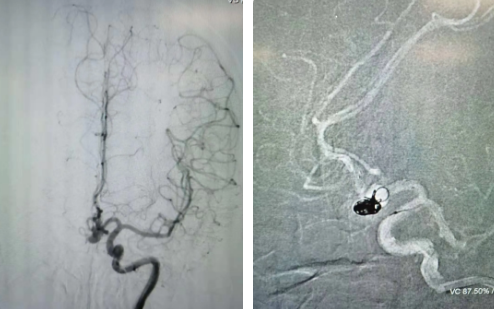

經(jīng)過全面仔細(xì)評估,西安國際醫(yī)學(xué)中心醫(yī)院神經(jīng)外科陸丹醫(yī)生決定采用微創(chuàng)介入進(jìn)行治療。在取得患者及家屬同意后,3月11日,陸丹醫(yī)生為患者行Atlas支架輔助顱內(nèi)動脈瘤栓塞術(shù)。

腦血管較外周血管更為脆弱、迂曲,對術(shù)者的操作技術(shù)及精準(zhǔn)性要求特別高。術(shù)中,陸丹醫(yī)生通過股動脈穿刺、置入微導(dǎo)管,再通過微導(dǎo)管將彈簧圏送入動脈瘤腔內(nèi),利用彈簧圈的機(jī)械閉塞作用,達(dá)到防止動脈瘤破裂的目的。術(shù)后,患者各項生命體征平穩(wěn)。

陸丹醫(yī)生介紹,此次腦科醫(yī)院首次采用Atlas支架輔助進(jìn)行顱內(nèi)動脈瘤栓塞術(shù)。以往動脈瘤栓塞術(shù)中的支架輸送導(dǎo)管較粗,支架順應(yīng)性差,易使載瘤動脈移位,而Atlas支架的輸送導(dǎo)管很細(xì),輸送順滑,同時順應(yīng)性及貼壁性強(qiáng),能夠適應(yīng)迂曲的腦遠(yuǎn)端血管。